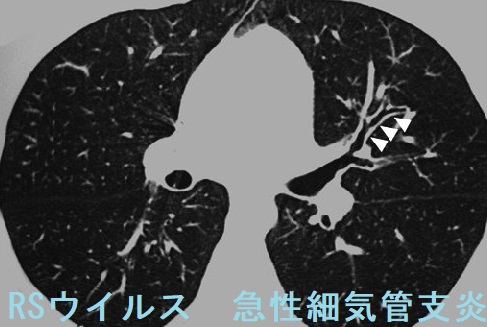

RSウイルス感染症は、小児呼吸器感染症の代表的なもので、風邪から肺炎まで重症度は様々です。上気道炎が下気道へ及び急性細気管支炎を来すと、

- 呼気性喘鳴(鼻水だけでなく、喘息様のヒューヒュー・ゼイゼイした喘鳴が聴こえる。下気道の狭窄による)

- 多呼吸、鼻翼呼吸、胸骨上部と肋間に陥没呼吸→呼吸困難

- チアノーゼ

が出現します。無呼吸発作、急性脳症に至る場合もあります。